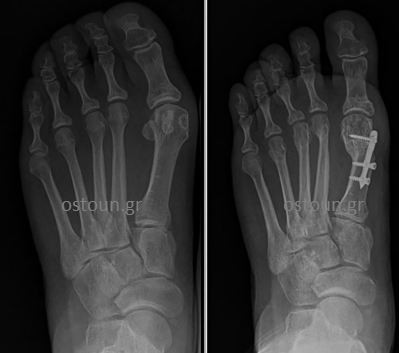

Στις διαδερμικές οστεοτομίες δεύτερης γενιάς αντιμετωπίστηκε το πρόβλημα της πλημμελούς συγκράτησης της οστεοτομίας. Έτσι, χρησιμοποιήθηκαν υλικά, τα οποία παρείχαν ισχυρή συγκράτηση και βοηθούσαν στη γρήγορη κινητοποίηση. Τέτοια υλικά ήταν ειδικά σχεδιασμένες πλάκες. Το μειονέκτημά τους ήταν ο μεγάλος τους όγκος, κάτι που δε συμβάδιζε με τη φιλοσοφία της ελάχιστα παρεμβατικής πράξης.

Διαδερμική τεχνική δεύτερης γενιάς με ογκώδη υλικά οστεοσύνθεσης